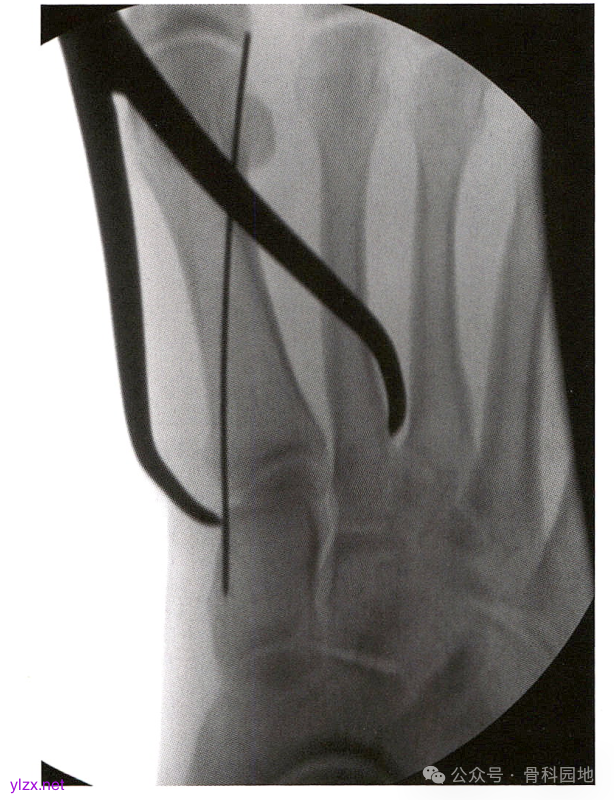

大多数损伤的第2MT都是向外半脱位的。将第2MT基底复位到第1MT基底外侧和内侧楔骨外侧关节面形成的凹陷中。在内侧楔骨的内侧皮质和第 2 MT基底外侧经皮放置一个中号复位钳,然后钳夹复位。

复位后,透视正位片和30°斜位片证实复位效果。